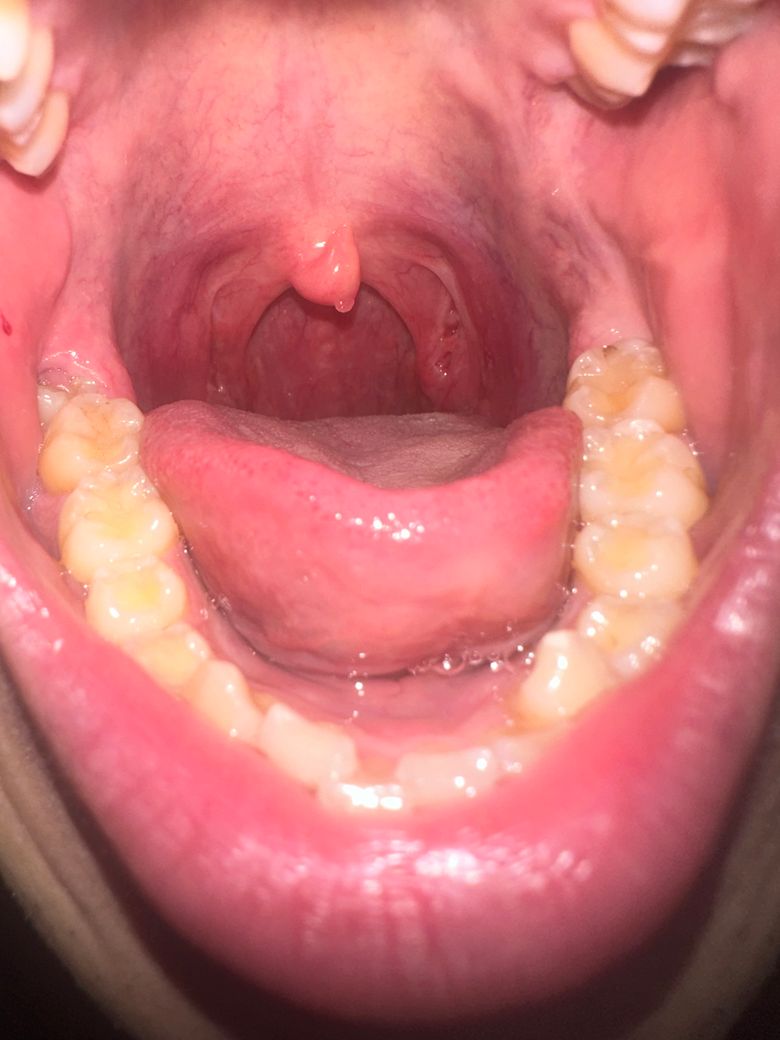

목젖 뒷면 혹이 있어서 확인 부탁드립니다.

올해 1월부터 목젖 뒷면에 혹이 관찰되었습니다.

아래 사진은 지금 사진이고요

점점 위치랑 보이는 면적이 변하는것 같아 문의드립니다.

근처 이비인후과에선 지켜보자고 했는데요.

• 1번 째 사진